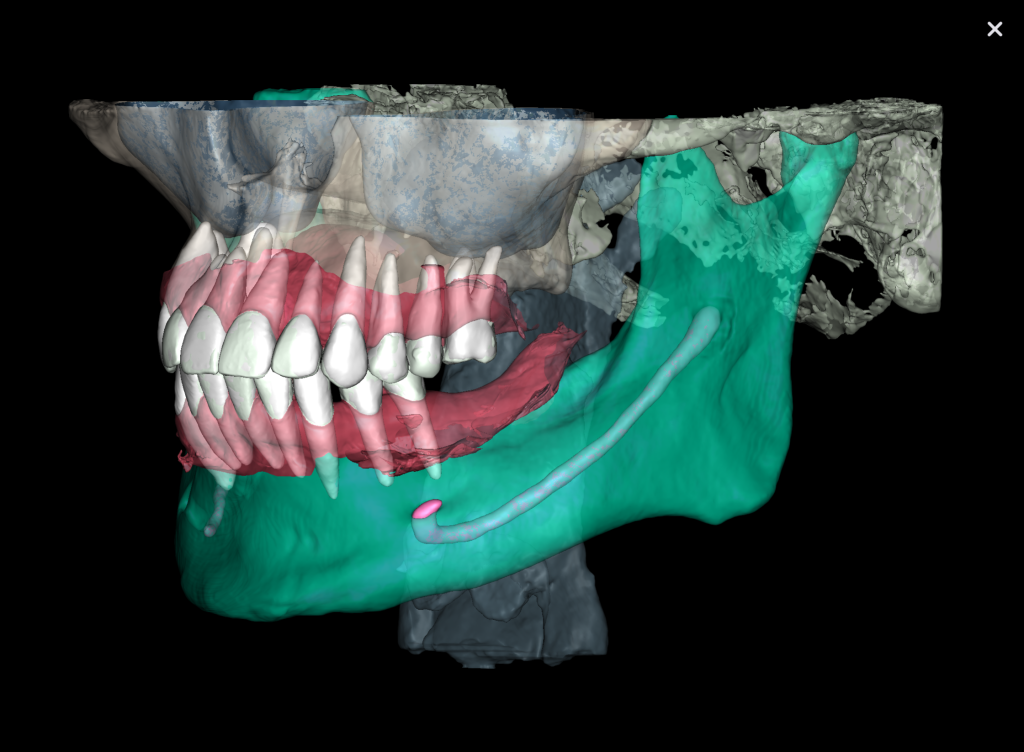

The decision has been made to perform immediate implant placement to replace teeth 24 (Universal 12) and 25 (Universal 13).The optimal position of the future implant is planned by starting with intraoral scanning and importing digital models into the Diagnocat STL module

3D reconstruction created on the basis of DICOM and an intraoral scan in the Diagnocat STL module allows you to choose the optimal size and location of the implants